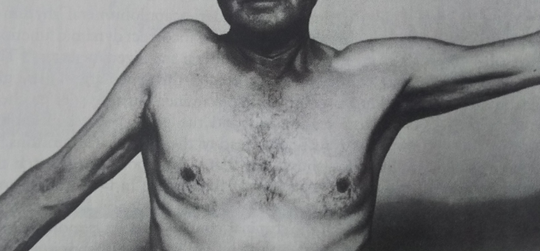

腕の拳上が即時に可能となる

大学3年生アーチェリー選手、2017年3月から弓を肩の高さに引き上げて保持できなくなる。腫れ、熱は無いが腕を横から挙げていくと60度蚊ら90度で痛みが生じ、120度以上は力が入らず180度腕が挙がらない。

近隣医科に行くほど日常生活にも支障なく放置して様子を見ていたが、症状不変。

棘上筋への置鍼(寸3、2番)、その後筋膜リリース3分間。施術時間7分間ほど。

直後効果として、ROM左右さ無く、上肢拳上に支障なし。その2週間後、施術後の状態が維持され、アーチェリー完全復帰。

骨・軟骨・靭帯損傷・神経損傷なく、筋・筋膜・腱の支障による症状の場合は可逆的変化は著明。物理刺激は即時反応を示すが、物理刺激をやめれば反応は消失するのが一般的である。しかし、本症例のように約6か月にも及ぶ傷害であっても、即時効果ならびに持続的効果が確認できた症例である。